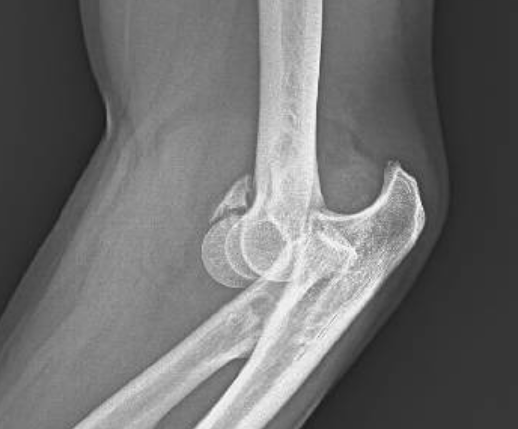

- Radiografía simple: las radiografías anteroposterior y lateral, antes y después de la reducción, son fundamentales para evaluar la congruencia articular y la presencia de fracturas (Figura 1).